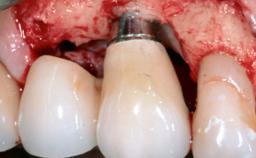

In this case, Nicola Zitzmann describes the sudden loss of a previously well-osseointegrated implant that had been in healthy function for 5 years. The case includes recommendations for occlusion and function of implant restorations. A 74-year-old patient had received implant-fixed dental prostheses in the maxilla in 2008, and in the right mandible three years later. His tooth loss was mainly related to recurrent caries associated with hyposalivation as a potential side effect of his cholesterol-lowering medication.